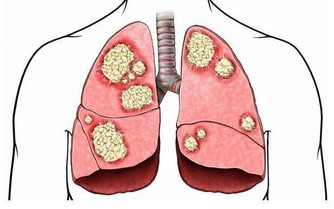

肝是「排毒工廠」,不養肝毒素堆成山

中醫學把肝比作「將軍之官」,民間更有「肝有病不長命」的說法。

可見,肝臟對人體的重要性。肝不好會引起哪些症狀呢?下面我們一起來看看。

肝不凈會怎樣

1、肝「苦」毛病多,各器官養分不足

中醫講,百病之源,根在肝臟。

如果肝臟代謝不正常,人體所需養分得不到及時供應,各個器官無法正常工作。

2、毒素滯留體內,臉色暗黃

體內產生的毒素、廢物等都需要肝臟排毒,

如果肝臟無法正常工作,毒素會滯留體內,再美的女性也會變成「黃臉婆」。

3、氣血不暢,代謝緩慢

肝臟幫助人體調節氣血,維持人體代謝正常;

如果肝氣疏泄不正常,氣血就會瘀滯;體內濕氣、毒素累積過多就會引起疾病。